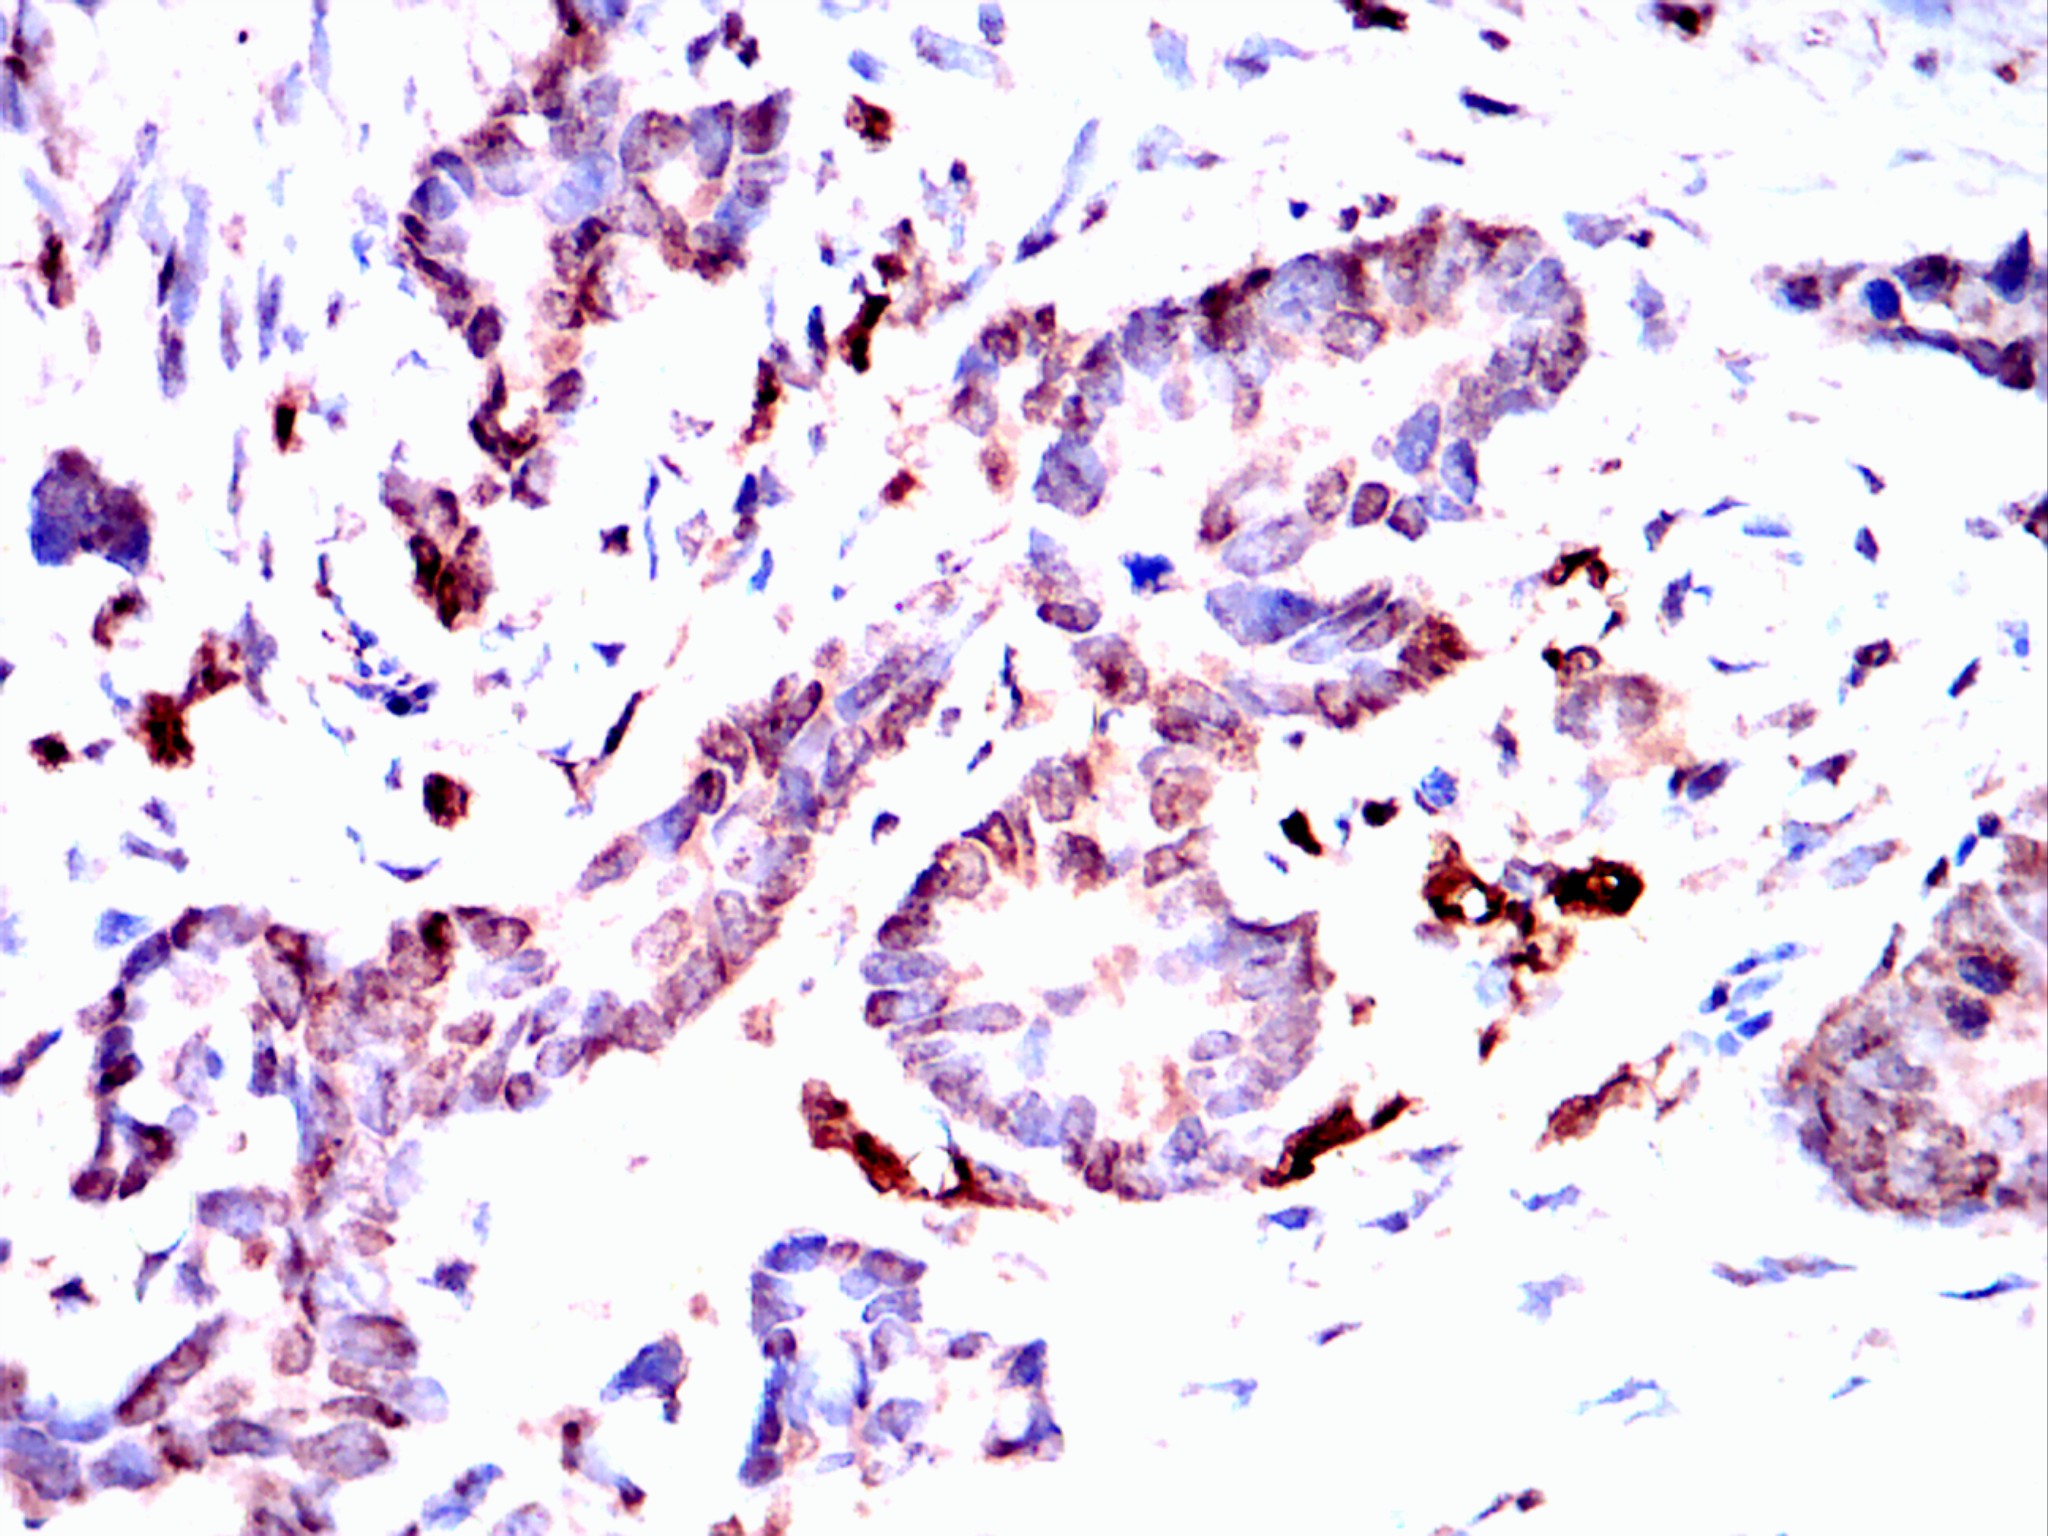

Immunohistochemical analysis of paraffin-embedded colon cancer tissues using Visfatin(PBEF) mouse mAb with DAB staining.